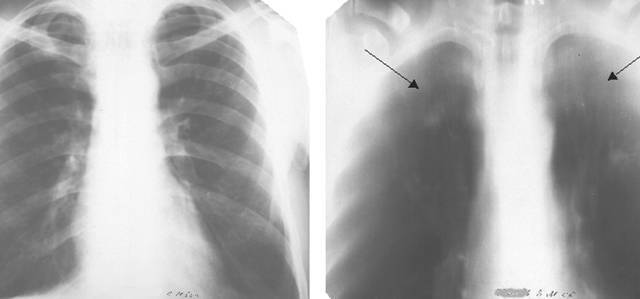

Иллюстрации по теме очагового и инфильтративного туберкулеза